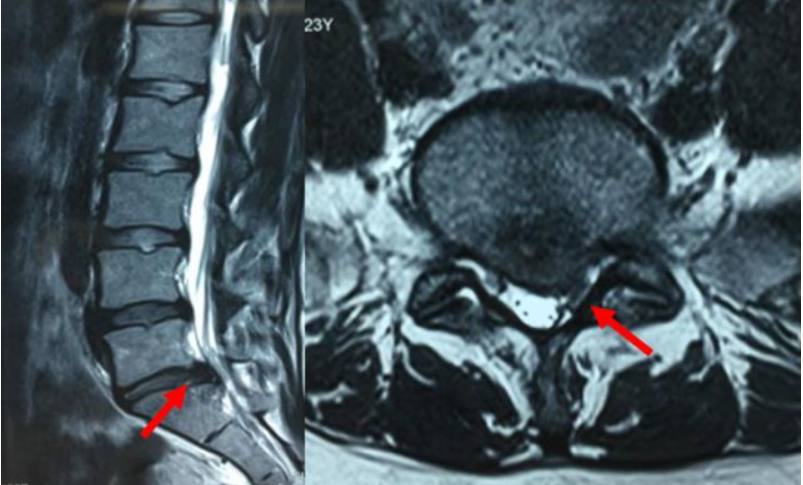

③腰椎磁共振(腰椎MRI)。

图片 14338